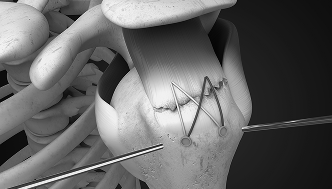

회전근개봉합술

반월상연골절제 봉합술